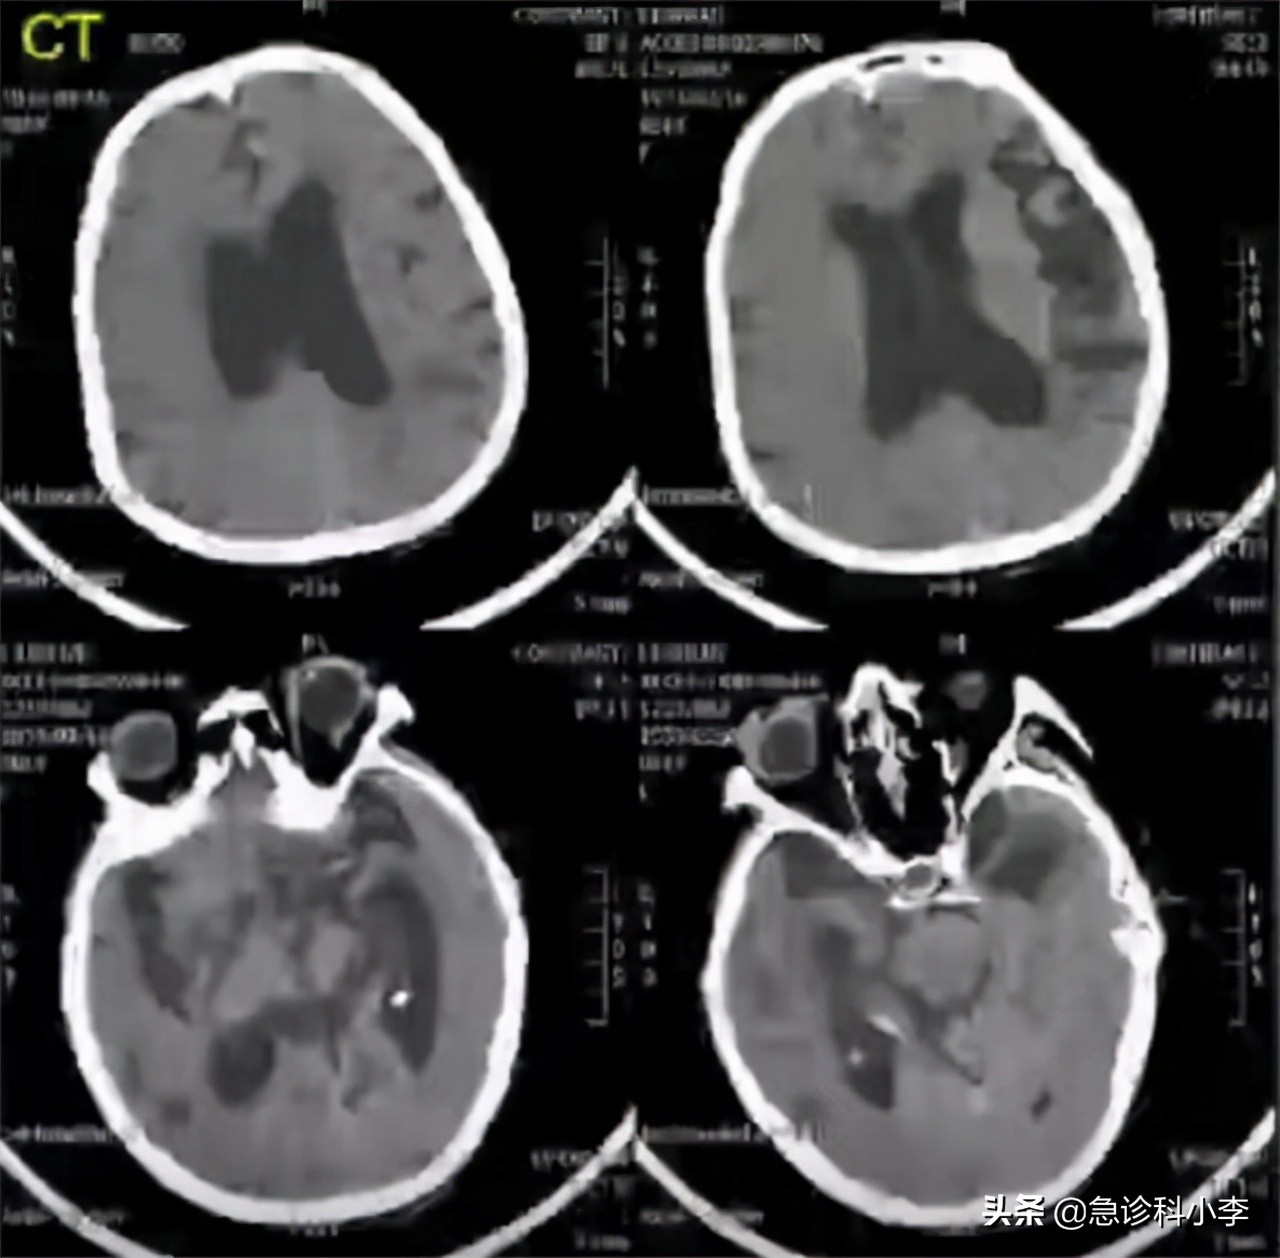

陈先生进入抢救室后,我们给他做了 急诊CT和MRI,排除了脑出血问题,但是发现了脑内多处梗塞灶, 确诊为脑梗死。

通过头颅彩超,我们发现 颅内动脉出现狭窄,颅内血流动力严重不足,确诊为急性脑缺血 ,我们通过静脉 溶栓治疗,疏通脑血管,缓解脑缺血现象和脑梗塞 。